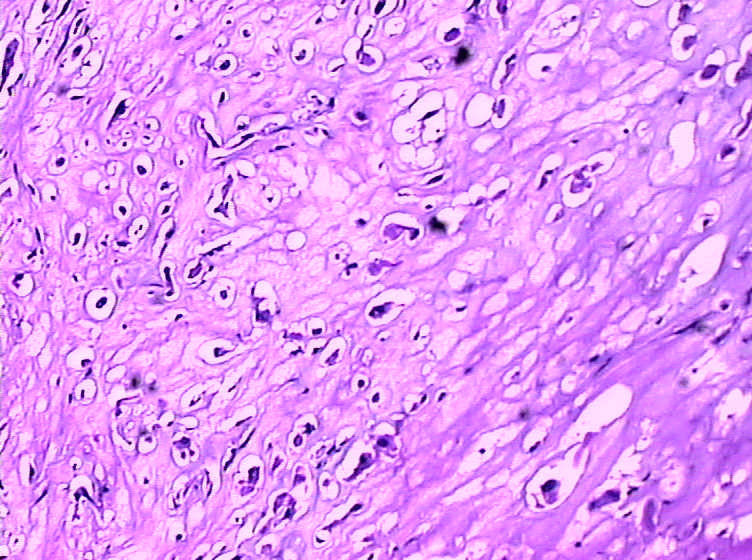

女,4岁,咽喉壁肿物。